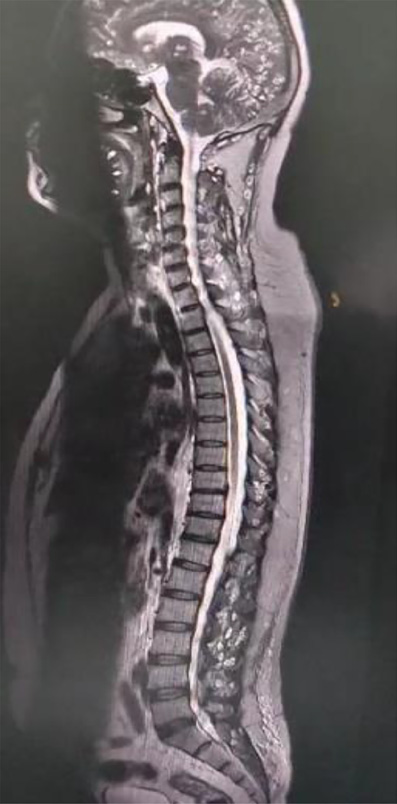

Spinal imaging demonstrated degenerative changes, including diffuse cervical disc bulges at multiple levels (C3–C7) and lumbar disc pathology at L4–L5, causing anterior thecal sac indentation but without cord compression or myelomalacia. While the spinal findings were incidental, they were clinically relevant as contributors to chronic pain and potential neurological deficits.

Spinal MRI revealed reversal of cervical lordosis with diffuse disc bulges at levels C3/4, C4/5, C5/6, and C6/7, causing mild anterior thecal-sac indentation but without evidence of cord compression or myelomalacia (Figures 4–7) [5]. The lumbar spine showed disc desiccation with a diffuse bulge at L4–L5, indenting the thecal sac yet preserving normal vertebral body height and marrow signal intensity. No paravertebral abscess, vertebral destruction, or compressive myelopathy was noted [6].